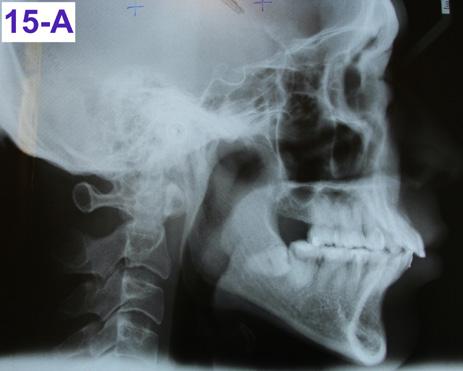

Lateral Cephalometric radiogram and tracing revealed robust lower airway (18.0/15mm), CVMS 6, maxilla and mandible are prognathic (SNA - 93° and SNB - 84°), Class II skeletal (ANB –9.0 mm, Witts – 9.0 mm). The patient was hyperdivergent (NS/ GoM – 30°, ALFH - 83 mm!!), protrusive maxillary incisors (U1/ SN – 117.0°), mandibular incisors were within the norm (L1/GoM 95.0°) and Harvold Δ was 30 mm. The soft tissue profile (lips) was convex (Figure 5-C, D).

Fig. 15A: Post-treatment, Cephalometric radiogram